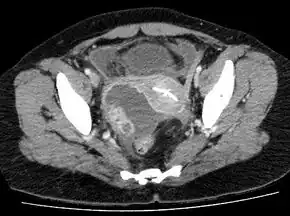

A tubo-ovarian abscess to the person's right of the uterus. The uterus contains an IUD.[14]

Laparoscopy and other imaging tools can visualize the abscess. Physicians are able to make the diagnosis if the abscess ruptures when the woman begins to have lower abdominal pain that then begins to spread. The symptoms then become the same as the symptoms for peritonitis. Sepsis occurs, if left untreated.[15]:103 Ultrasonography is a sensitive enough imaging tool that it can accurately differentiate between pregnancy, hemorrhagic ovarian cysts, endometriosis, ovarian torsion, and tubo-ovarian abscess. Its availability, the relative advancement in the training of its use, its low cost, and because it does not expose the woman (or fetus) to ionizing radiation, ultrasonography an ideal imaging procedure for women of reproductive age.[8]